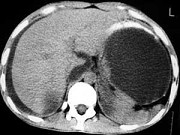

- 单项选择题男,33岁, 腹部外伤后2月余,腹部疼痛, 行CT扫描所见如图,最可能的诊断是 ( )

C、胰腺创伤性假性囊肿